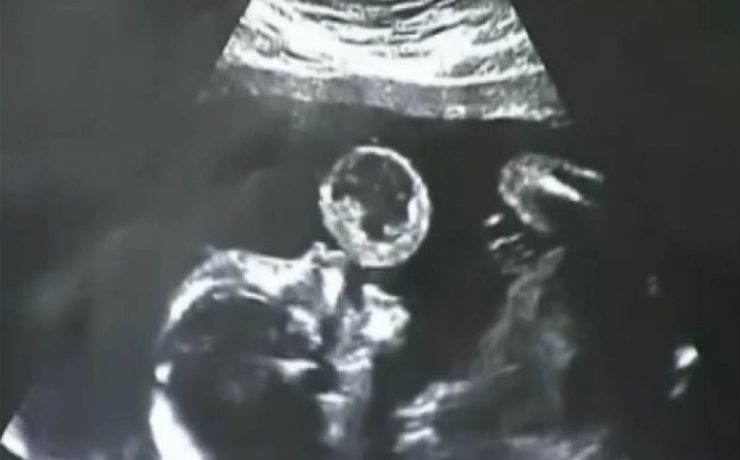

Hiperplasia prostática benigna

La hiperplasia prostática benigna (HPB) es muy prevalente en atención primaria; es el principal motivo de consulta por problemas urológicos en el hombre y es el primer diagnóstico que debemos pensar ante un paciente mayor de 50 años que consulta por síntomas obstructivos y/o irritativos. El diagnóstico de HPB es